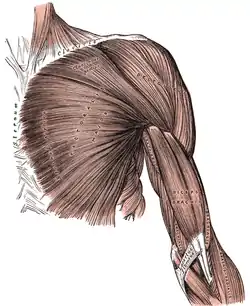

The procedure is performed through a deltopectoral approach, in which the space between the deltoid muscle and pectoralis major muscle is developed. The subscapularis muscle, one of the four muscles of the rotator cuff, is typically detached to perform the operation. The native humerus and scapula bones are prepared using precise machining to accommodate their respective implants. At the end of the procedure, the subscapularis muscle is typically repaired, although some surgeons advocate not repairing this muscle due to the excess tension placed on it by the altered mechanics of the reverse shoulder design.[7]